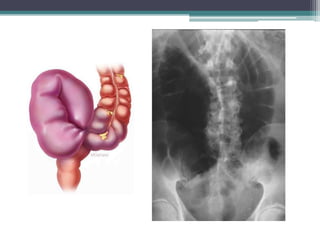

Tài liệu bàn về tắc ruột, bao gồm định nghĩa, phân loại và nguyên nhân của tình trạng này, với sự phân biệt giữa tắc cơ học và cơ năng. Các triệu chứng và chẩn đoán lâm sàng được trình bày, kèm theo phương pháp chẩn đoán cận lâm sàng như x-quang và siêu âm. Ngoài ra, tài liệu cũng đề cập đến các biến chứng và hậu quả của tắc ruột.